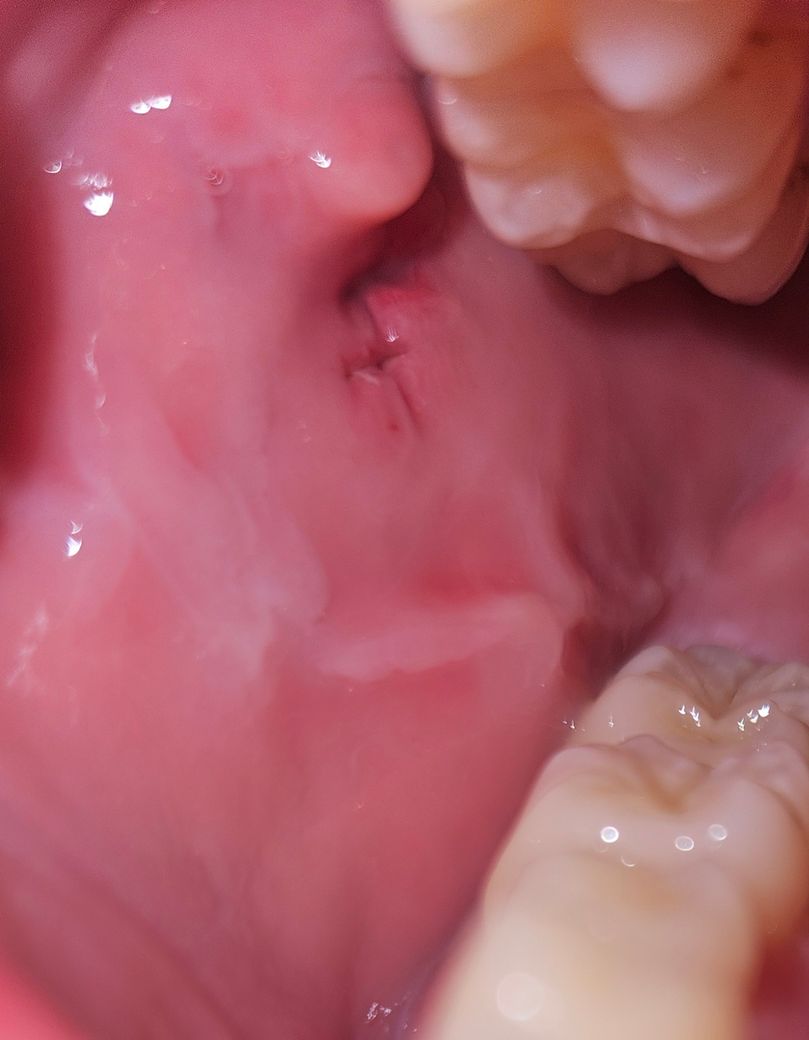

입안 점막 실밥은 다 녹았는데 상처는 벌어져있어요 다시 꼬매야할까요?

7일전 쯤 입안에 볼쪽 점막 절개하고나서

오늘 보니 실밥이 다 녹고 떨어졌더라고요

근데 상처는 아직 벌어져있는데

이거 다시 꼬매야 할 정도인가요?

현재 상태로는 문제가 될 정도로 잇몸이 크게 벌어져 있거나 하지는 않습니다. 다시 꼬맬 필요까지는 없는 상태로 보입니다.